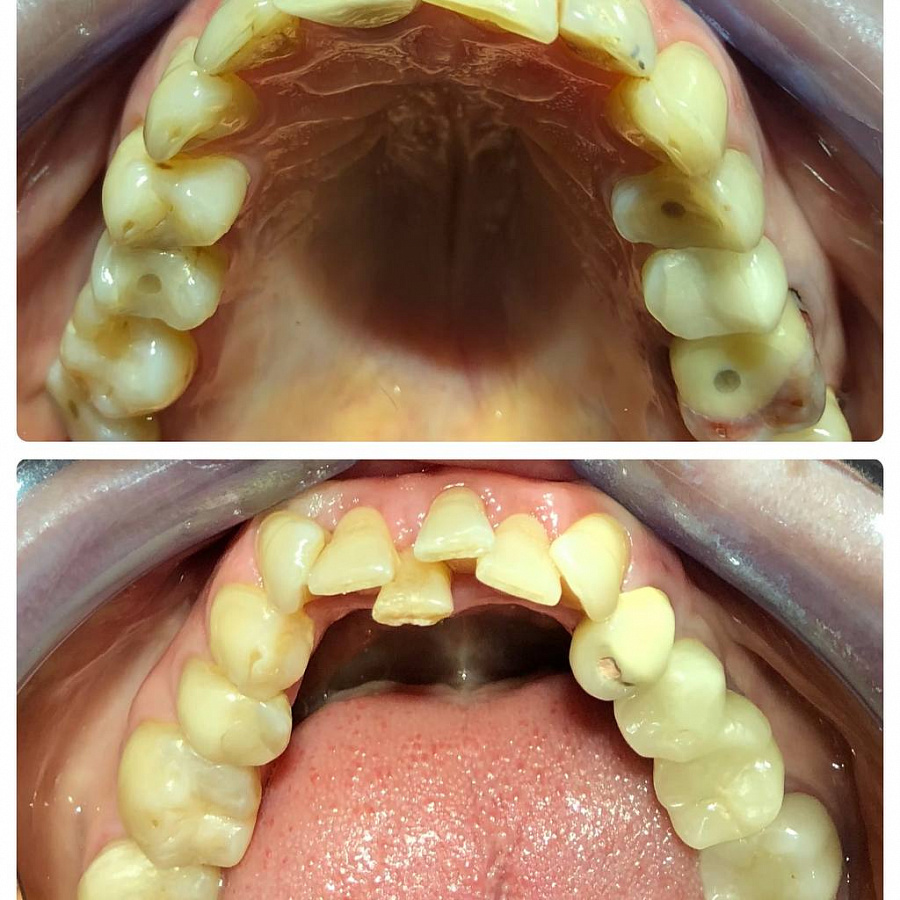

Пациентка обратилась с жалобами на эстетику всех зубов. Ранее уже были установлены постоянные коронки, имплант 34.

После диагностики пациентке было предложено провести комплексное лечение:

1. Санацию полости рта.

2. Ортодонтическое лечение.

3. Ортопедическое восстановление окклюзионных контактов и эстетики зубов.

Санацию проводил доктор Платонов. Далее провели удаления резца и ортодонтическое лечение с помощью брекетов, чтобы додготовить зубы к протезированию.

После доктор Мискевич провела протезирование, чтобы нормализовать прикус, изменить цвет и форму зубов.